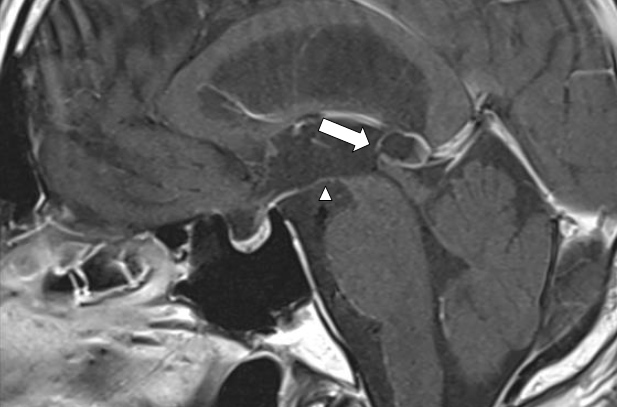

Figure 5 Postoperative magnetic resonance imaging showed the perforated area of the cyst (arrow), and third ventricle (arrowhead).